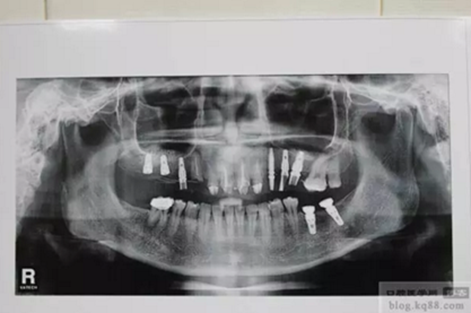

上圖為術(shù)后1年X光片 上基臺

雙側(cè)種植牙分別做成連冠、前牙做成單冠,左下6、7連冠,(戴牙后照片)